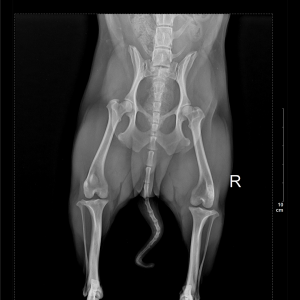

Not gonna lie, today was ruff. Up most of the night with Nichol. He is not doing well and Iām questioning all my life choices about why I did this to him. Iāve got an amazing support network here already with Landon and the staff at the school plus my amazing ā¤ļøhubs and ā¤ļøkids back home rallied around both Nichol and I as I worked through it. I did not go into school today. I took Nichol to the vet. In my copious preparation I had already sourced out two trusted, capable and English speaking Ā veterinarian clinics before coming here. The staff at east west confirmed my choices as the best so I reached out to both for an appt ASAP! Animal Mama responded quickly and they could See him that morning so I made my appointment for 10 AM. I caught a Grab and was there right on time. Iām super super impressed with the care he received, they were kind and patient and knowledgeable. I canāt ask for more than that. The vet was concerned about his hips and his knees. He took x-rays and determined his hips are great but he has one bad knee with a hyper mobile patella. The 22 hours on the flight with extended time not being able to walk around was more than his knee was able to tolerate. So inflammation and pain were the result. He prescribed 10 days of Meds and he predicts we will be on the mend shortly. All this for $57.50! And supposedly this is the āexpensive āvet in town. I am more than happy to pay that as you canāt even walk into a vet in America for less than $100 Let alone get x-rays and meds!

They emailed me his X-rays! I hope I donāt embarrass him by sharing this, but look at his curly tailš¤©